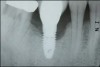

The entry of inflammatory cell infiltrate into the connective tissue (Figure 1 and Figure 2) differentiates peri-implantitis from peri-implant mucositis.1 Unlike a natural tooth—where periodontal fibers, transepithelial fibers, and gingival fibers absorb this exudate—none of these fibers are present around an implant (Figure 3). This allows the inflammatory cell exudate to directly enter the bone, resulting in bone loss and concomitant soft-tissue loss (Figure 4).1

Fig 1. In the pathogenesis of peri-implantitis, inflammatory cell infiltrate enters the connective tissue.

Figure 1

Fig 2. Inflammatory cell exudate enters right into the bone.

Figure 2